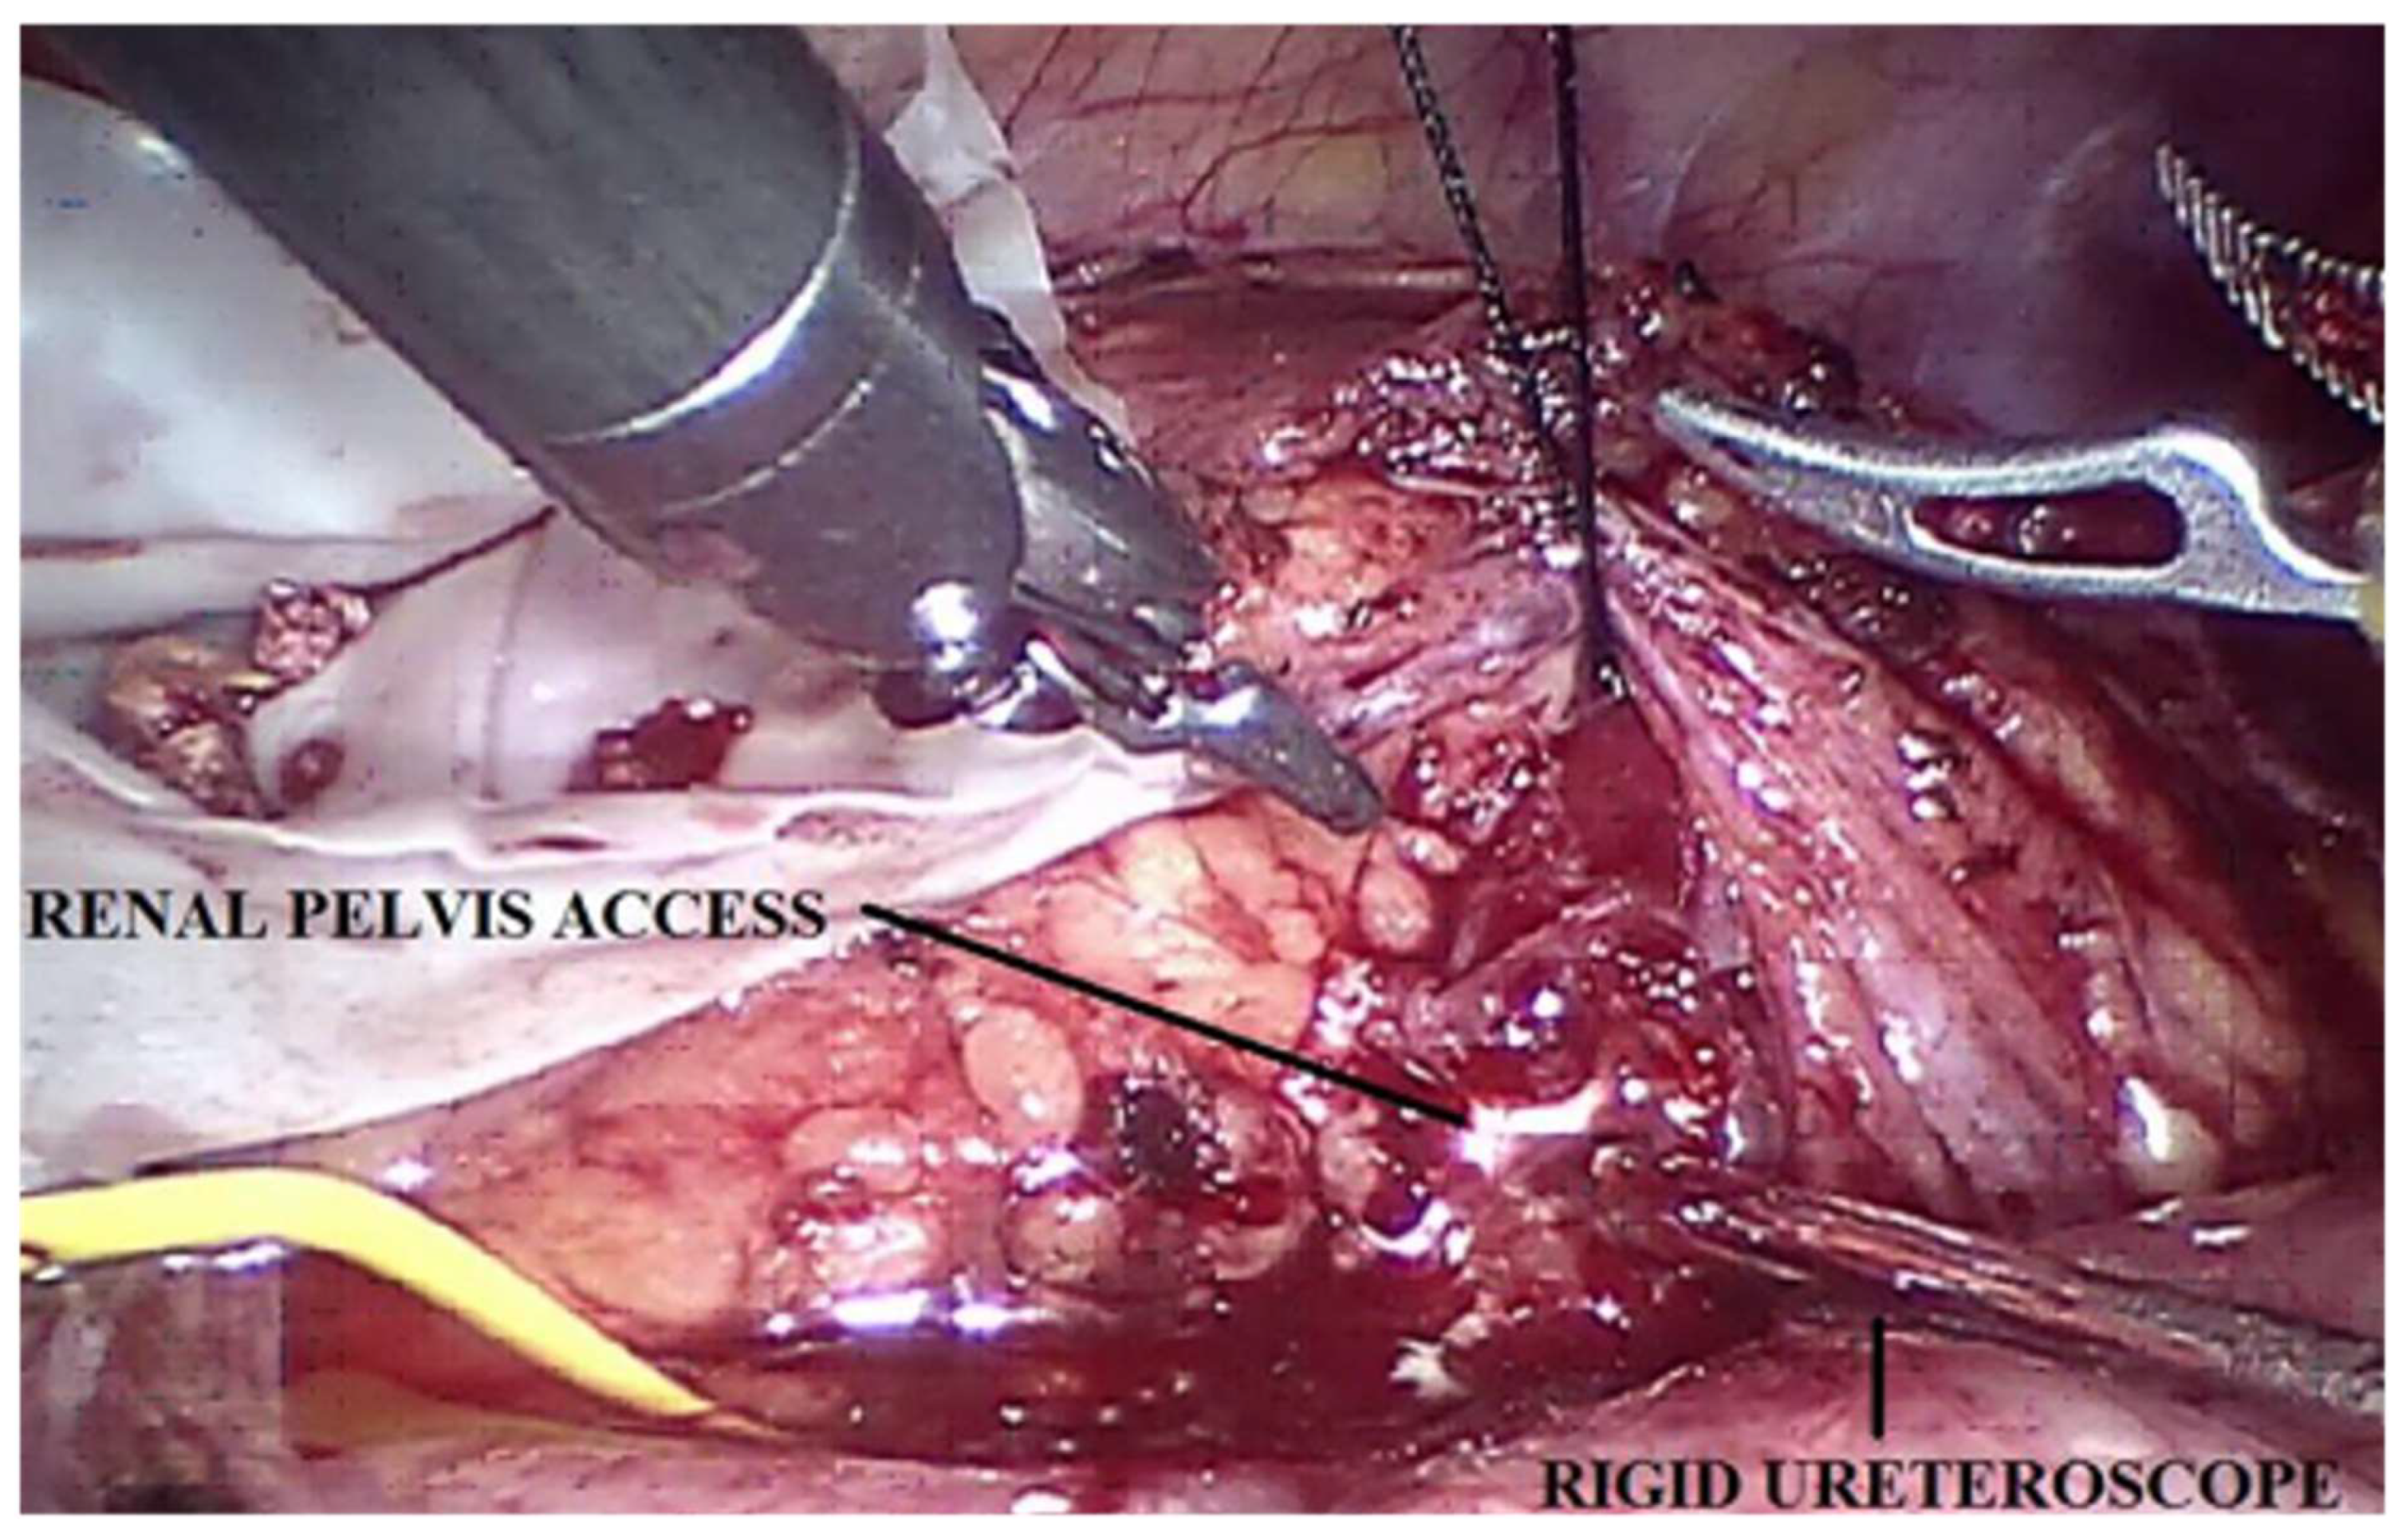

In all patients, a robot-assisted pyeloplasty was performed. In the two (29%) patients in whom nephrolithiasis was present, stone clearance was performed. In one case, the stones were simply removed by widening the renal pelvis incision and extracting them from the lower calyces (Figure 2). In the second case, once the renal pelvis was opened, a rigid ureteroscope (Ch 10) was inserted through the accessory laparoscopic port of 5 mm in the pelvis; nevertheless, the calyces that resulted were not easy to reach. Through the same trocar access, a flexible renoscopy was performed using a digital disposable flexible instrument. Without further increasing the pressure, irrigation of saline was used to permit viewing of the pelvis and calyces; the second robotic arm made it possible to maintain suction. A second stone was later identified, which was removed with a Dormia basket. Since the fact that the stones located in the medium and inferior calyx were larger than the circumference of the neck of the calyx, the extraction with the basket was not feasible. We performed lithotripsy with a Holmium laser through a 0.27 mm fiber. The mean operative time was 160 min (range 140–240 min). The average bladder catheter dwell time was 2 days (range 2–3 days), while the average abdominal drainage dwell time was 2 days (range 2–4 days). The mean hospitalization time was 4 days (range 3–9 days). On average, after 45 days (range 30–65) the JJ ureteral stent was removed cystoscopically.

Figure 2.

Robot-assisted approach to a patient affected by UPJO associated with nephrolithiasis. This technique permits us to easily perform a pyeloplasty and to clear the renal stones at the same time.